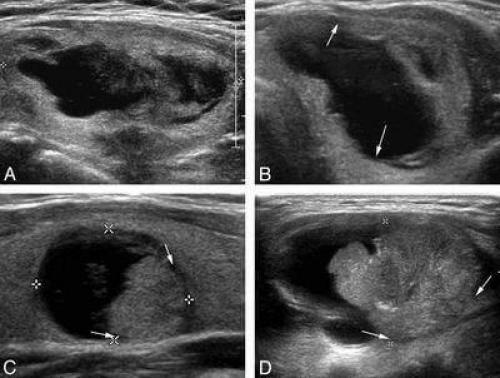

Стоит отметить, что по УЗИ нельзя установить является ли узелок раковой опухолью. Наибольшие опасения у врачей вызывают узлы, которые плохо отражают ультразвуковую волну, имеют нечеткие и неровные края, неоднородную структуру и в которых хорошо развито кровообращение.

Признаки настораживающие в отношении рака щитовидной железы на УЗИ

- Пониженная эхогенность.

- Реже – образования имеют изоэхогенную плотность.

- Неоднородная структура (за счет кистозной дегенерации или обызвествлений).

- Нечеткие наружные контуры (отсутствует ободок отграничения от окружающей паренхимы органа).

- Многоузловая структура.

- Неправильная форма образования.

- Дорсальное ослабление УЗ-сигнала.

- Наличие микро- и кальцинатов в опухоли.

- Деформация одной или обеих долей железы.

- Гиперваскуляризация образования с наличием патологической сети сосудов.

- Реже – понижение и отсутствие кровотока в патологическом образовании.

- Увеличение регионарных лимфоузлов.